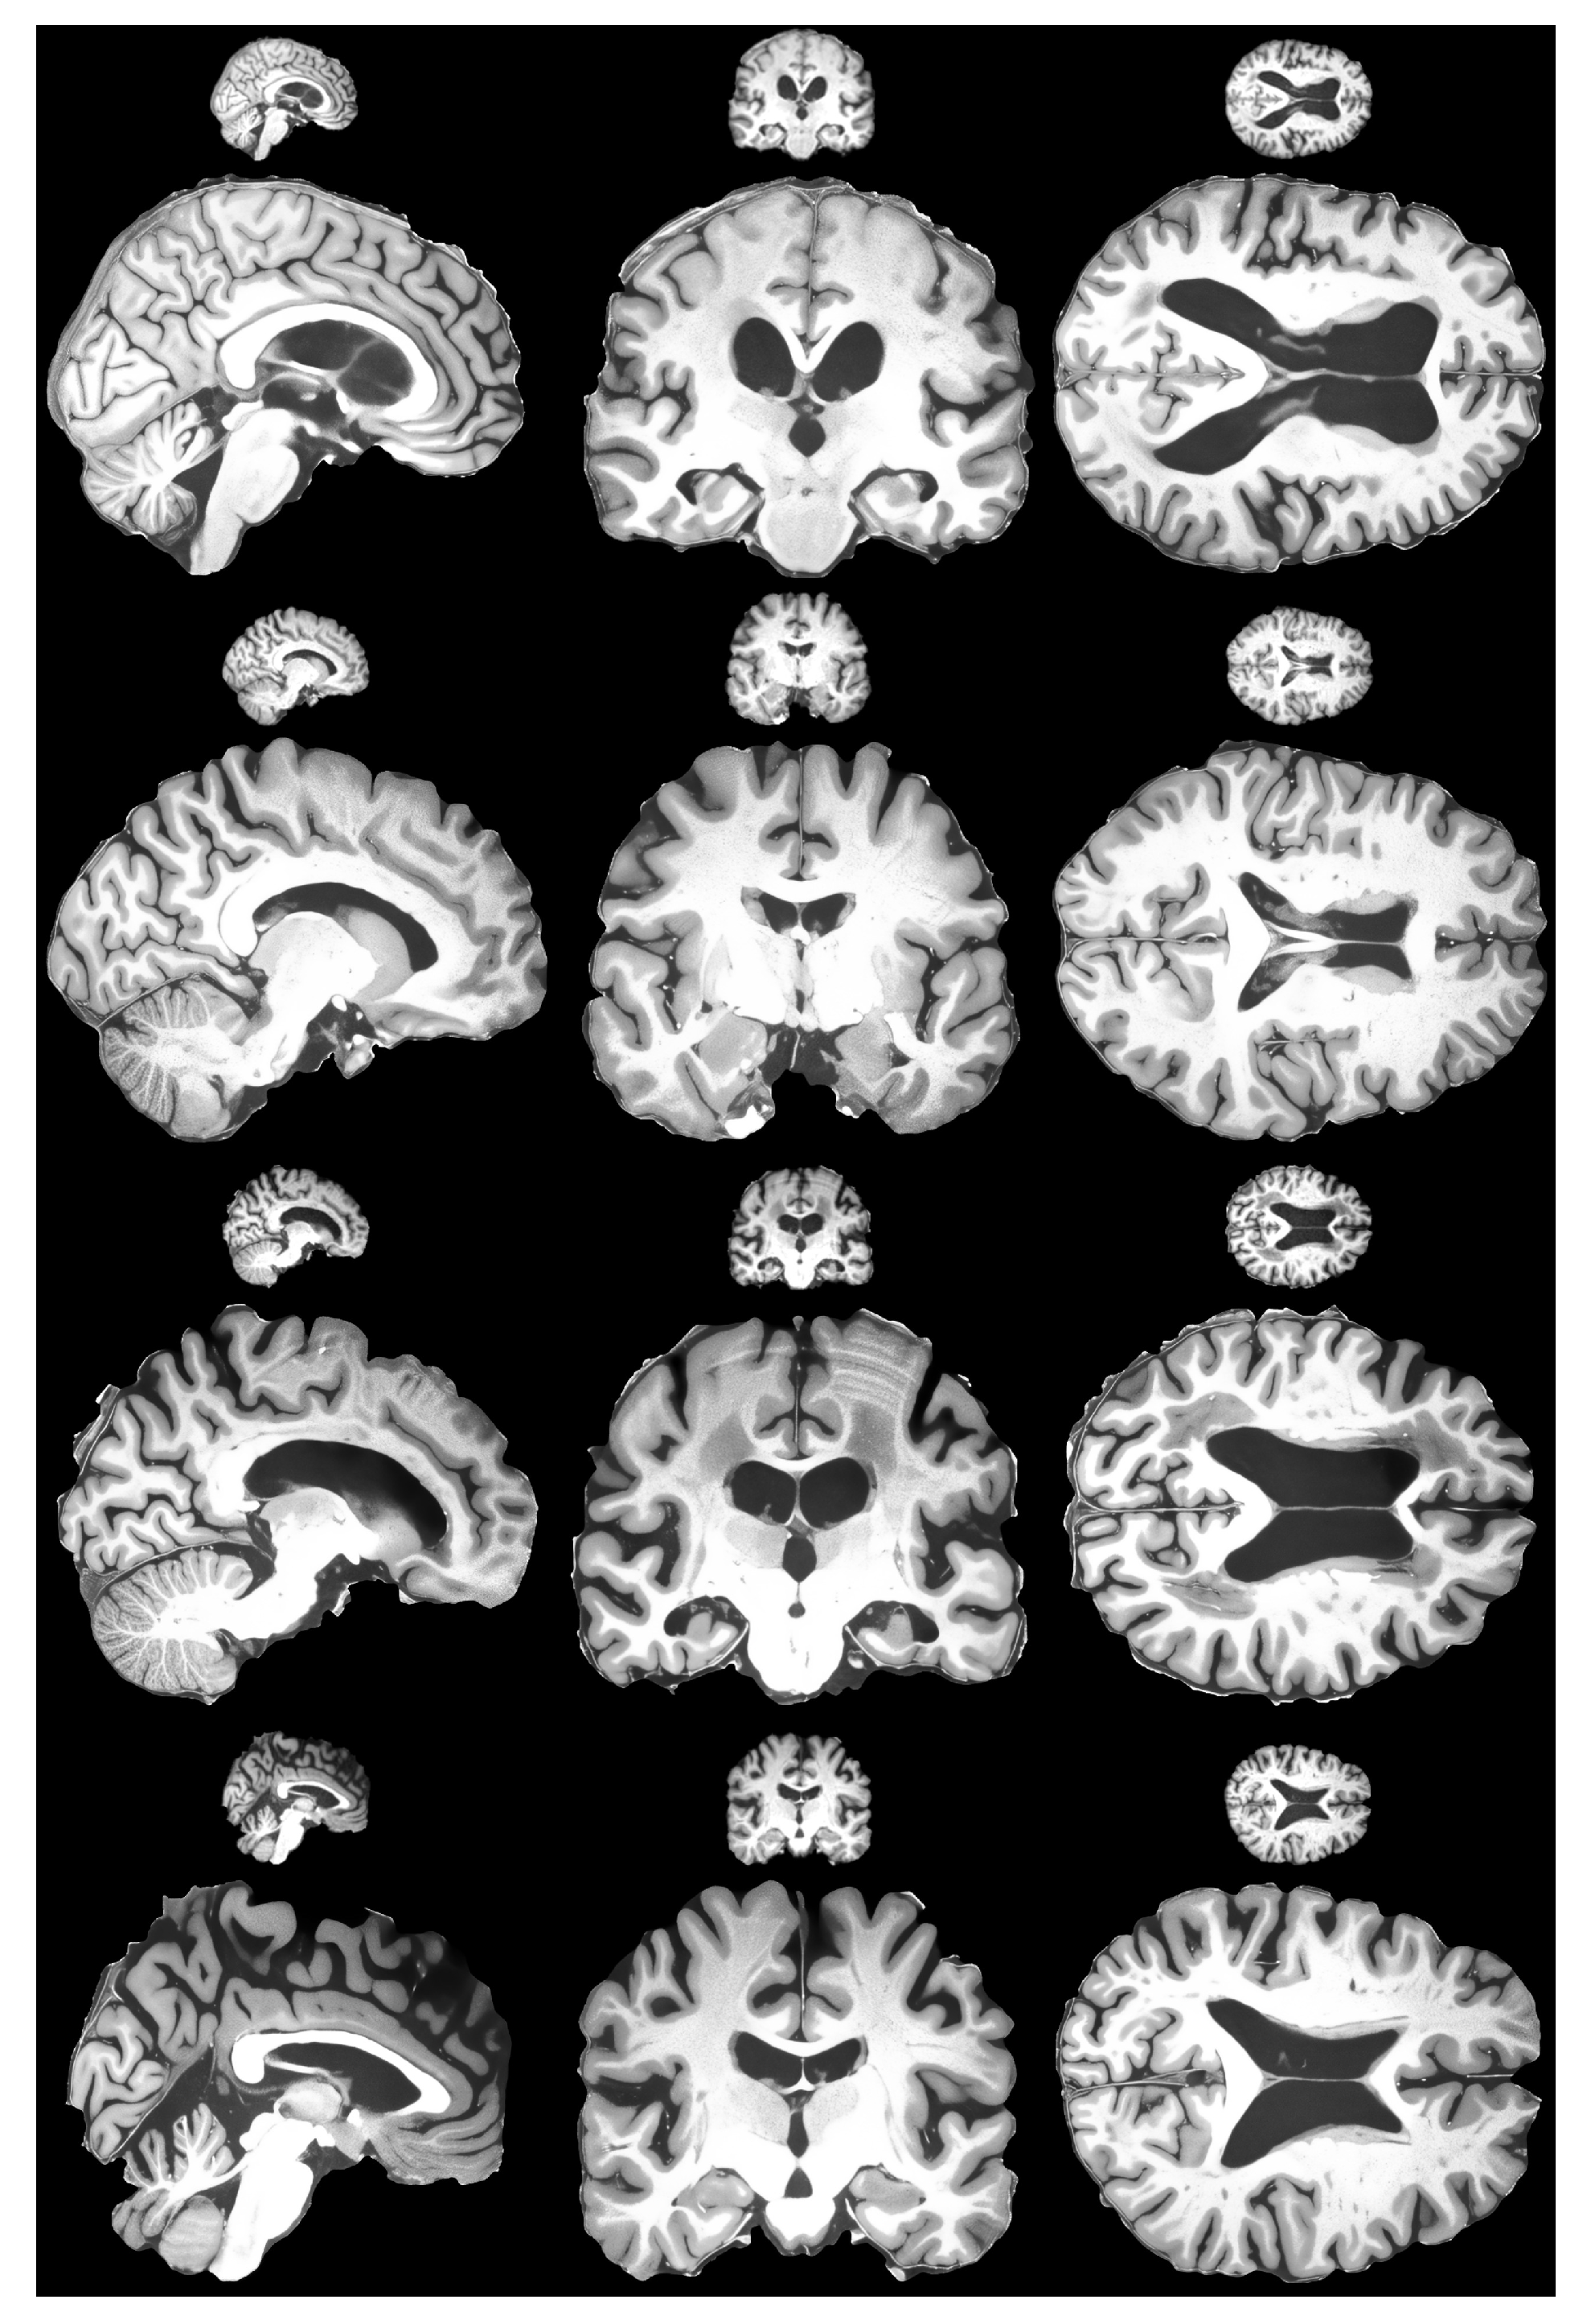

4.1. Experimentation Data

- Lusebrink, F.; Mattern, H.; Yakupov, R.; Acosta-Cabronero, J.; Ashtarayeh, M.; Oeltze-Jafra, S.; Speck, O. Comprehensive Ultrahigh Resolution Whole Brain In Vivo MRI Dataset as a Human Phantom. Sci. Data 2020, 8, 138. [Google Scholar] [CrossRef]